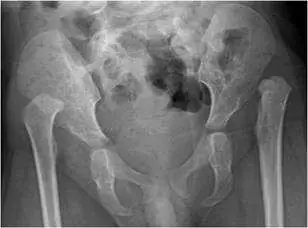

第一張(骨盆正面 AP 觀):

- 可見完整骨盆正面影像,包含薦髂關節、恥骨聯合、兩側髖臼及股骨近端。

- 左側髖關節:股骨頭(femoral head)向外上方移位,位置偏高,未能良好嵌入髖臼(acetabulum)內,髖臼頂部較淺,骨化程度可見,形態扁平。

- 右側髖關節:股骨頭位置亦有偏移跡象,顯示可能為雙側受影響,但程度可能不同。

- Shenton 線(Shenton's line):自股骨頸內側緣至恥骨下枝下緣應形成連續平滑弧線,此案可見左側 Shenton 線明顯中斷,提示髖關節半脫位或脫位。

- 髖臼指數(acetabular index):髖臼頂部角度增大,顯示髖臼發育不良(acetabular dysplasia)。